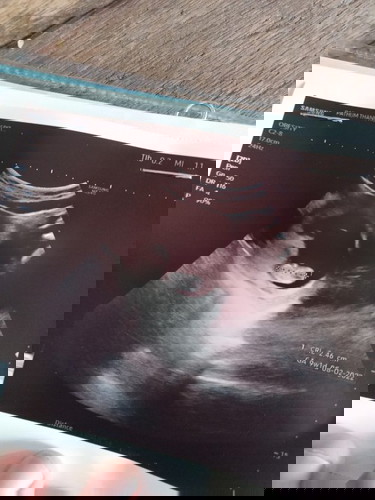

อยากรู้ว่าเขายึดหลักอะไรเวลาวัดอายุคครรภ์จากประจำเดือนไม่มาหรือจากการอัลตร้าซาวด์คะพอดีหาหมอแล้วขึ้น9วีค1วันแต่ในสมุดสีชมพูเขียน10วีค4วัน

การอัลตราซาวด์คลาดเคลื่อนได้ค่ะ เพราะคำนวณจากขนาดตัวและน้ำหนักของน้อง ไม่ตรงเป๊ะๆค่ะ